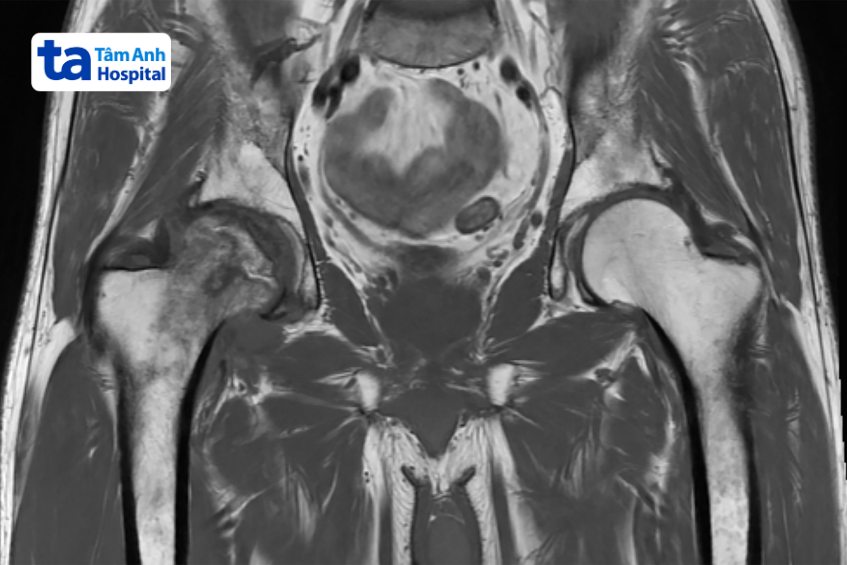

Chụp cộng hưởng từ (MRI) được đánh giá là phương pháp chẩn đoán hình ảnh viêm khớp háng hiện đại và cho kết quả chính xác cao. Kỹ thuật này sử dụng sóng radio và từ trường, tạo ra hình ảnh có độ tương phản cao và chi tiết giúp bác sĩ có thể phát hiện những tổn thương về cấu trúc và hình thái ở khớp háng nói riêng và các bộ phận khác trong cơ thể nói chung. Riêng về chẩn đoán viêm khớp háng, chụp MRI có vai trò quan trọng trong việc hỗ trợ bác sĩ đánh giá cấu trúc phần mềm và cấu tạo khớp háng như sụn khớp, bao khớp…